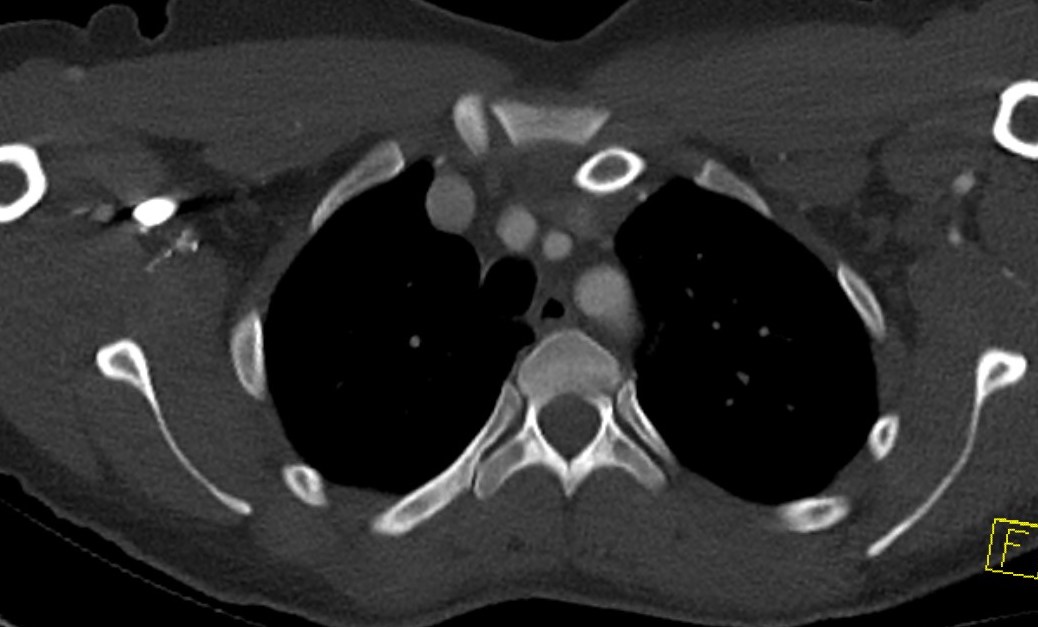

Left posterior SCJ dislocation with pre- and post angiogram

Left posterior SCJ dislocation with pre- and post angiogram

Severe left posterior SCJ dislocation with subclavian vein compression